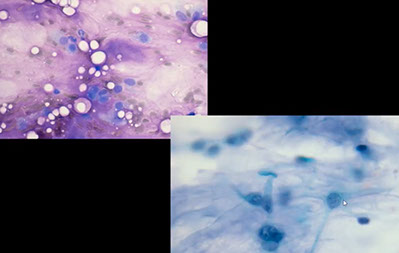

Mucinous cyst contents only, AUS. Turned out to be mucoepidermoid carcinoma

Mucinous Cysts

Includes malignant neoplasms (MEC), inflam dz, and acquired cysts (mucoceles [pseudocyst bc no epithelial lining] and retention cyst [has lining]

Micro: Hypocellular c lots of mucin, histiocytes (muciphages), scattered inflam, amylase (needle-shaped) crystals

Low-grade MEC

Mucoepidermoid Carcinoma (MEC)

MC (minor and major) salivary gland malignancy in kids and adults; usually in parotid and sometimes in palate or buccal mucosa; in 6th decade, but can be all ages

- low grade tumors are more cystic and present as painless soft cystic mass (commonly recurs); FNA shows bland mucus-producing glandular cells, muciphages, cyst content and lots of mucoid material

- higher-grade tumors are more solid and infiltrative c more sx (skin changes, pain, nerve damage) c FNA showing obviously malignant cells similar to non-K SCC, and glandular cells and intermediate cells c rare mucus and possible necrosis and mits

Cyto: Single and loosely grouped pleomorphic mucinous (glandular) cells found in low-grade tumors are cuboidal to columnar c irreg nuclear contours, coarse and clumped chromatin and prominent nucleoli and can be similar to muciphages, goblet cells or signet-ring shaped c lots of mucin;

- intermediate cells present in both low and high grade are relatively small c inc NC, small round nuclei, vesicular chromatin, inconspicuous nucleoli, and look like metaplastic squames or glandular cells, similar to reactive ductal cells

- high-grade tumors have lots of squamoid / epidermoid cells (hyperchromatic nucleus and dense orangeophilic cytoplasm) and intermediate cells that are bland and smaller c less cytoplasm

- mucin present in background

- clear cells present often